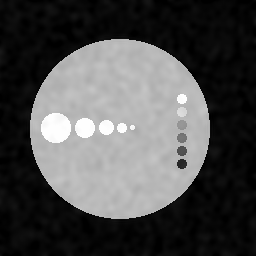

Images simulées : à gauche, haute résolution type IRM ou scanner X, à droite, base résolution type PET.

Après correction des effets de volume partiel par analyse multirésolution et fusion on obtient :

Le contour des disques est mieux délimité sans que l'information à l'intérieur ne soit dégradée. Ainsi les activités moyennes dans les 11 disques sont retrouvées avec une précision au moins aussi bonne que la méthode de référence* qui ne fait que de la correction quantitative sur des régions d'intérêt sans corriger les images proprement dites.